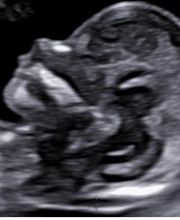

Lo Studio Medico Ginecologico della Dott.ssa Francesca Calonzi è situato a Viterbo in Largo Nagni 15. Lo studio completamente rinnovato è dotato di sistemi diagnostici di ultima generazione e si avvale della collaborazione di molteplici medici specialisti e figure paramediche, per offrire un servizio completo di diagnosi e cura nei vari ambiti. La Dott.ssa Calonzi, specialista in Ginecologia e Ostetricia si è laureata e specializzata presso lUniversità degli studi di Roma Tor Vergata. Dal 2017 esercita presso lospedale Santa Rosa di Viterbo e offre assistenza nella donna in gravidanza sia nelle gravidanze fisiologiche che nellambito della patologia ostetrica, dalla fase preconcezionale al postpartum. Presso lo studio ginecologico inoltre è possibile effettuare visite volte a valutare il benessere generale della donna dalla fase adolescenziale alla menopausa.